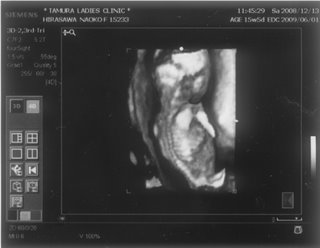

お腹の赤ちゃんは、今日で24週と4日。あっという間に7ヶ月突入です

![]() お腹もドンドン、食欲もドンドン出ていてあしたの4回目の検診コワーイ ![]() 妊娠発覚から三ヶ月半、なのにもう妊娠7ヶ月!頭がついていきません ![]() でも、毎日激しくなる胎動に感激している日々です ![]() 一回目の検診から4週後、2度目の検診に行ってきました。 2008年12月13日 赤ちゃんは15週と5日 ![]() 順調でした ![]() 左側から頭、胴体、足が写っていまーす ![]() 今回は4Dの機械も入り毎回撮影してくれるそうでーす ![]() 赤ちゃんは、ゴツゴツした背中だけを 見せ、顔はみせてくれませんでした~ ![]() それから4週後、3回目の検診。 2009年1月10日 赤ちゃんは19週と5日 ![]() 336gくらいになったようです ![]() 4D ようやく顔をみせてくれました ![]() かなりエイリアン ですが、フニュフニュ可愛かったです![]() 性別が わかりそうだったんですが、ソラ同様肝心なトコロをみせてくれませんでした ![]() もちろんどっちでもいいんですが、しりたーい ![]() 明日わかるかな ![]() ソラも赤ちゃんがテレビに映ったり、雑誌に載っていたり、 出かけ先で見かけたりすると、「ベイビー ![]() 」と大きな声で、何度も何度も興奮気味に言います ![]() 自分もまだまだ赤ちゃんなのに、「ベイビー」は自分より 小さくて可愛いものだと感じ始めているようです ![]() わたしは、一週間に1度だけ1歳になったばかりの 女の子を預かっています。 ソラは、その子が自分のオモチャを使うことに対して 少しイヤな気がしているようです ![]() 少し前までは「ドーゾー」と相手に有無を言わせず 何でも渡していたけど、どんどん自我が出てきているみたいですね~ そんな感じでオモチャを取り合いしながら、シェアすることも学んでいます。 でも女の子が寝ると、さすがに可愛いと思ったらしく、 頭をナデナデ、チュしていました ![]() 妊娠検査薬で妊娠反応がプラス |